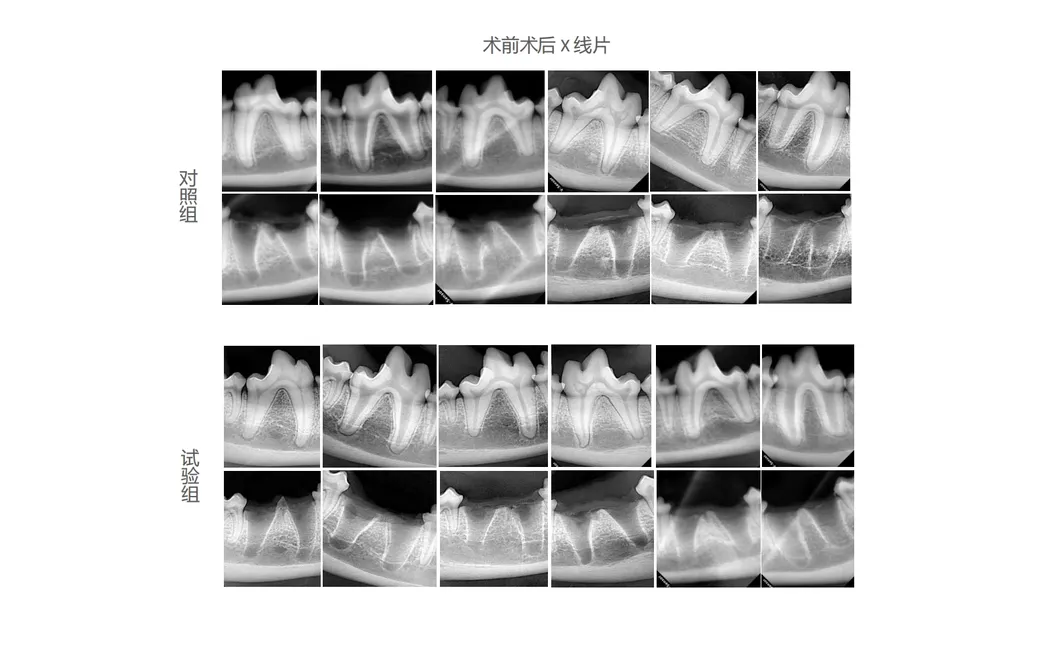

In this study, dogs were selected as subjects to evaluate the effectiveness of pioneering dental tools. The treatment group utilized the Golden Cudgel-Pneumatic Dental Elevator Kit. Researchers documented physiological parameters, extraction duration, and socket damage. Comprehensive imaging and histological evaluations provided statistical insights into the kit's superior performance compared to traditional manual devices.